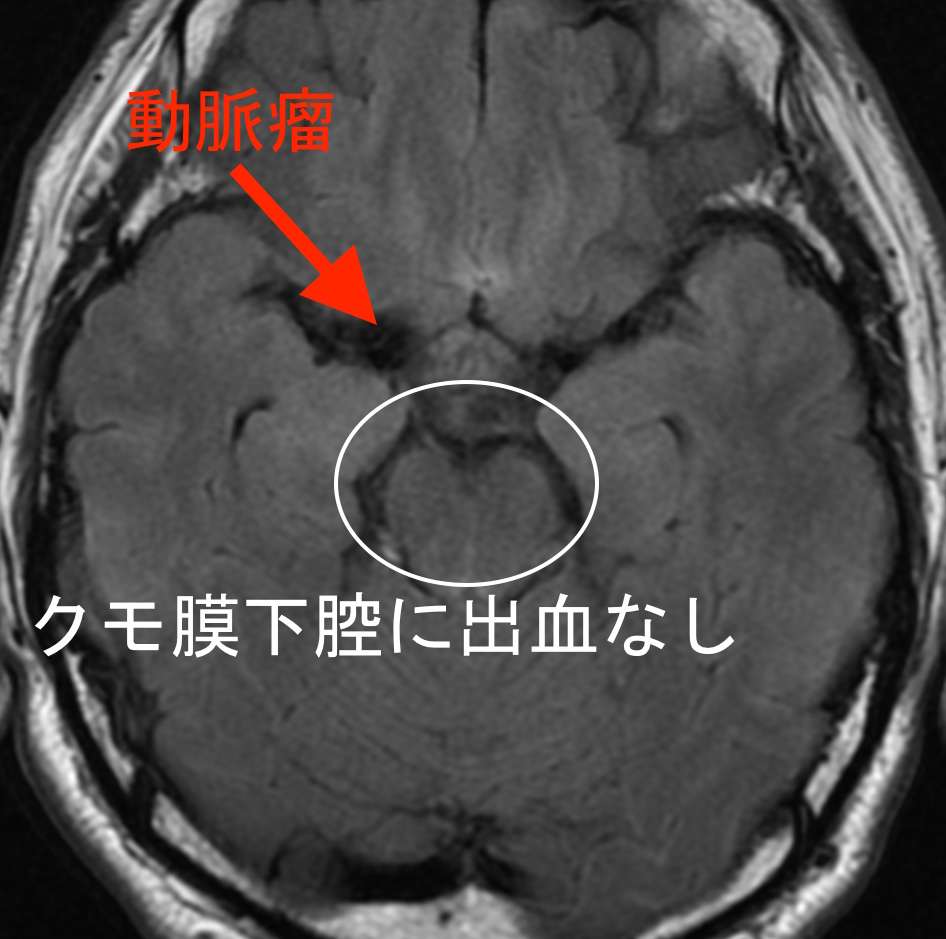

症状の特徴から群発頭痛と診断しましたが、頭部MRI検査を希望されたので施行しました。

MRAで、右中大脳動脈に直径約5cmの巨大脳動脈瘤が見つかりました。破裂した場合、くも膜下出血を起こす危険があります。

しかし、頭部の断層画像では、出血した形跡はありませんでした。